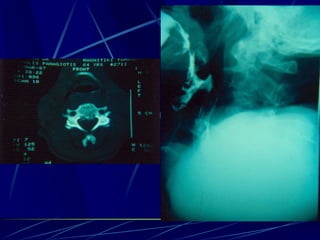

Φυματίωση της σπονδυλικής στήλης